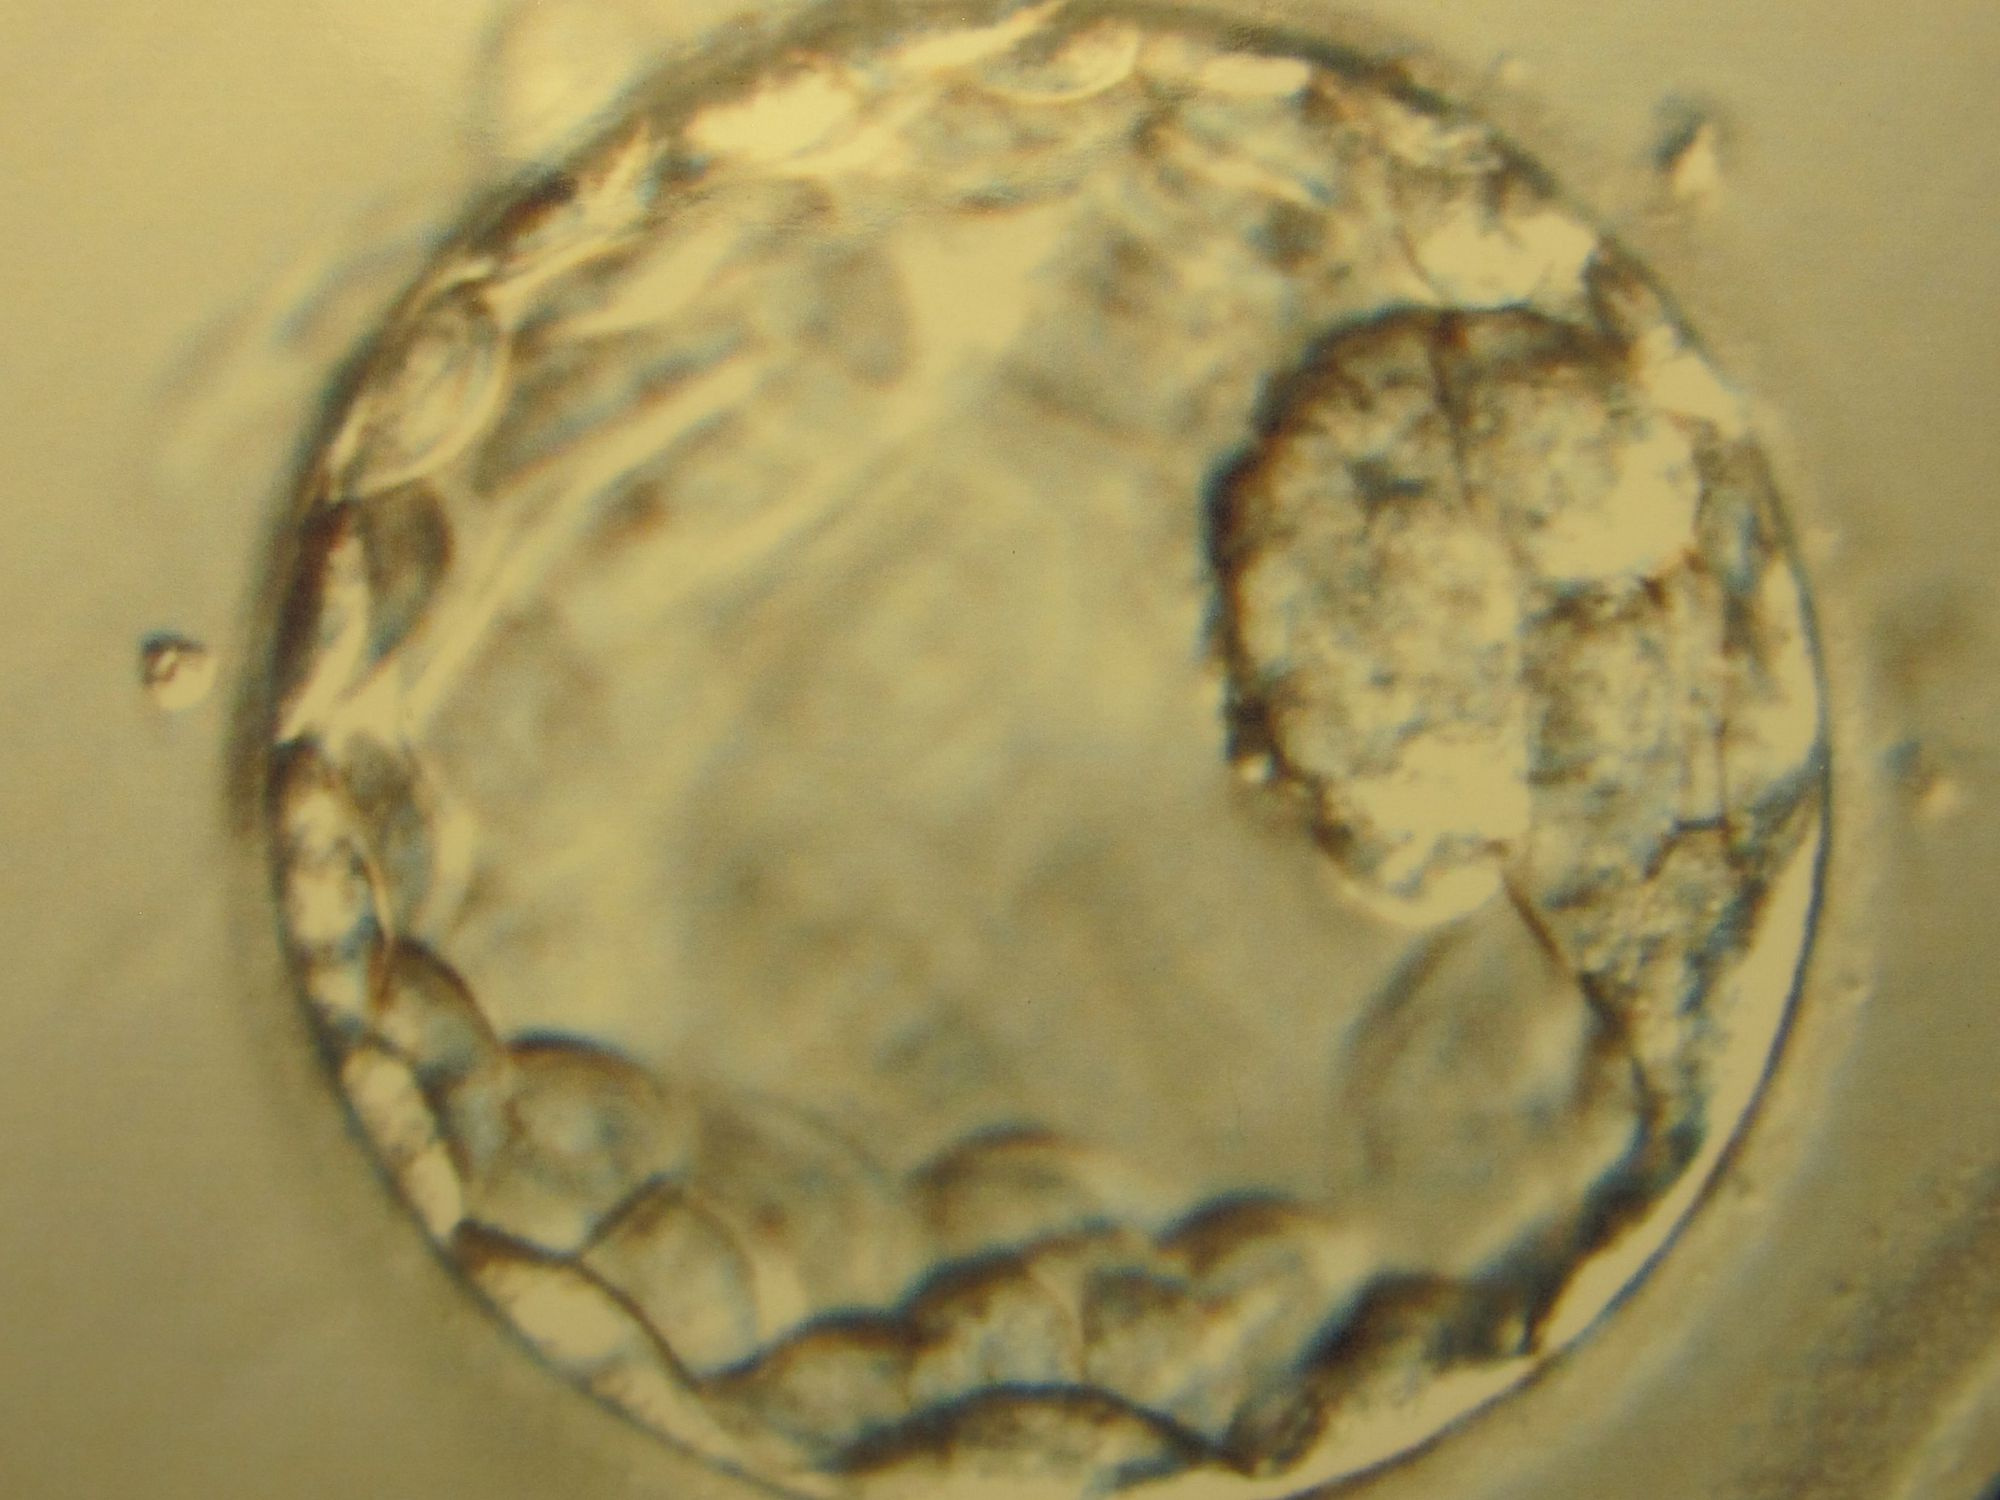

5 мая 2016 года ученым удалось довести зародыш до стадии бластоцисты и поддерживать его жизнедеятельность в течение 13 дней. Это на день меньше, чем позволяют законы Великобритании.

В двух параллельно опубликованных статьях в журналах Nature и Nature Cell Biology описывается эксперимент ученых Кембриджского университета и университета Рокфеллера, в котором человеческий эмбрион впервые прошел in vitro стадию бластоцисты.

После оплодотворения сперматозоидом человеческая яйцеклетка начинает делиться; в течение недели развивается кластер клеток, которые делятся на три группы: из одной развивается будущее тело ребенка, вторая формирует плаценту и связывает зародыш с материнским организмом, третья обеспечивает зародыш питательными веществами до того, как по плаценте пойдет поток материнской крови.

На седьмой день происходит прикрепление зародыша к стенке матки. Если этого не происходит, зародыш не выживает; ошибки этого процесса приводят к значительному проценту ранних выкидышей. В этом году ученым впервые удалось продлить срок жизни зародыша в пробирке: исследователи подобрали среду, в которой клеткам зародыша хватает питательных веществ и кислорода. Методика, разработанная профессором Кембриджского университета Магдаленой Зерникой-Гетц, была ранее опробована на мышах.